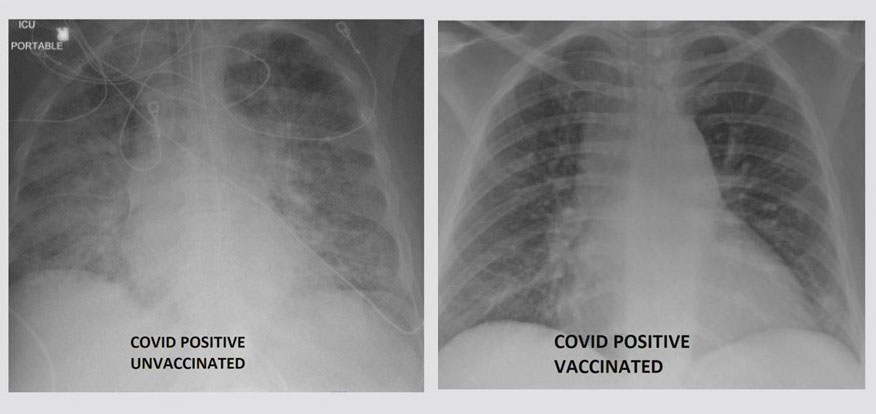

왼쪽은 백신을 맞지 않은 상태에서 코로나19에 확진된 폐의 모습. 오른쪽은 백신을 맞은 상태에서 코로나19에 확진된 폐의 모습. 왼쪽이 오른쪽보다 흰 부분이 많다. (사진제공=KSDK)

미국 미주리주 소재 세인트루이스대학병원 산하 의료센터 SSM헬스 집중치료실장인 가산 카멜 박사는 지난달 30일(현지시간) 현지 TV 방송 KSDK에 출연해 각기 다른 두 장의 폐 X레이 사진을 보여줬다. 하나는 코로나19 백신을 맞았으나 확진받은 환자의 것이고 나머지는 접종하지 않은 상태에서 감염된 환자의 것이었다.

카멜 박사는 두 사진을 비교·공개하는 것과 관련해 백신 접종 여부에 따른 극명한 차이점이 뭔지 보여주기 위함이라고 설명했다.

카멜 박사가 공개한 두 사진 가운데 백신 접종을 마친 환자의 것은 대개 검은색으로 표시됐다. 이는 폐포에 공기가 가득하다는 뜻이다.

반면 백신을 맞지 않은 환자의 폐 사진에는 하얀 부분이 많았다. 이를 폐음영(lung opacity)이라고 한다. 공기가 희박하다는 뜻이다. 폐포가 공기로 가득 차 있어야 하는데 공기 대신 유체(流體), 박테리아, 면역계 세포로 가득 차 있는 것을 말한다. 따라서 환자는 산소를 정상적으로 공급받을 수 없다.

카멜 박사에 따르면 이런 환자에게는 심지어 생명유지장치 같은 의료상의 도움이 필요하다. 그는 "이런 환자에게 최소한 산소를 공급해줘야 한다"며 "산소 외에 삽관, 진정제 투여 같은 다른 것이 필요한 경우도 있다"고 설명했다.

하지만 백신을 접종했는데 코로나19로 확진받아 입원했다면 대부분 그렇게까지 집중적인 치료는 필요하지 않다.